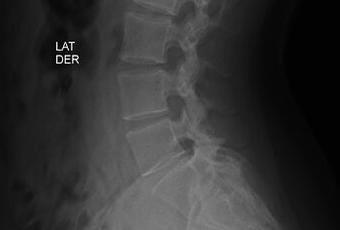

RADIOGRAFIA AP Y LATERALES DE COLUMNA LUMBAR

HALLAZGOS:

-Tejidos blandos, con densidad y morfología respetada, sin evidencia de lesiones.

-Columna vertebral, central. Sin listesis. Lordosis lumbar, con aumentos angulación.

-Cuerpos vertebrales con altura preservada, sin evidencia de lesiones líticas, blásticas o perdida de la contigüidad.

-Plataformas vertebrales, con adecuada densidad y morfología.

-Pedículos, laminas posteriores sin evidencias de lesiones líticas, blásticas o perdidas de la contigüidad.

-Apófisis transversas de L5, con fusión de apófisis derecha con sacro, y apófisis transversa izquierda con longitud mayor a 19 mm. Resto de apófisis espinosas, transversas y facetas sin evidencias de lesiones líticas, blásticas o perdidas de la contigüidad.

-Espacio intervertebrales, con adecuada amplitud.

-Neuro forámenes, con diminución de su amplitud en L5-S1, resto con adecuada amplitud.

OPINIÓN RADIOLÓGICA:

EL PRESENTE ESTUDIO RADIOGRAFICO, CON HIPERLORDOSIS LUMBAR.

SACRALIZACIÓN DE L5 CASTELLVI TIPO IV.

APARENTE ESTENOSIS DE NEURO FORÁMENES DE L5-S1.

CORRELACIONAR CON DATOS E HISTORIA CLINICA DEL PACIENTE.